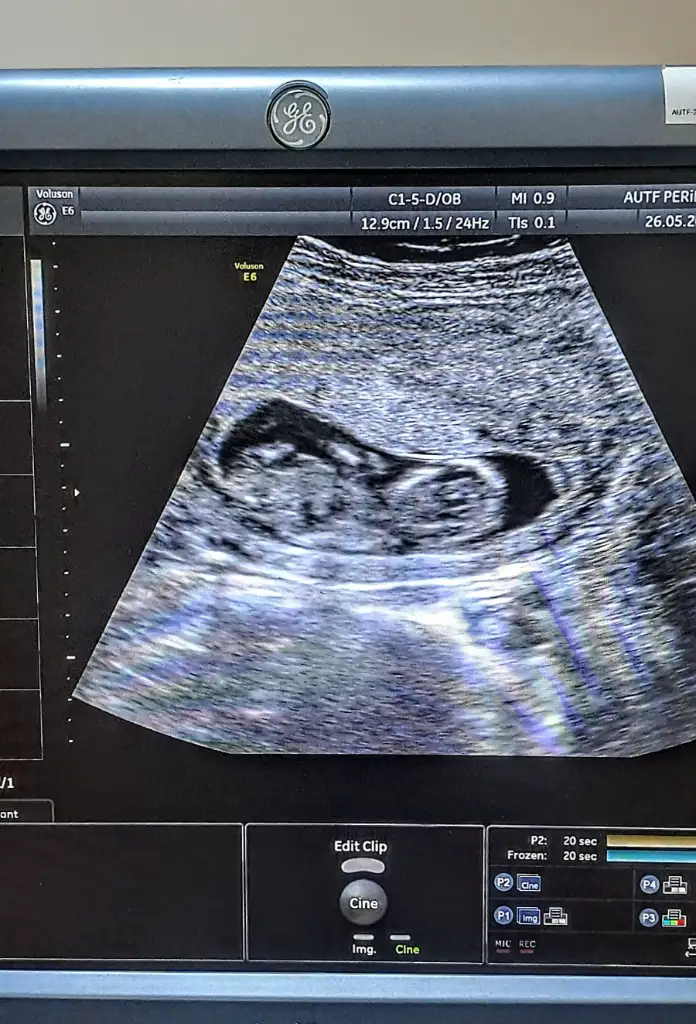

Doktor 17 haftaya girerken iki kez yüzde 80 kız dedi daha sonra 18+2 de gittim %99 erkek dedi bu şekilde olan değişen varmı 22 haftada detaylı ultrason giricem iyice muallakta kaldım

Tahminde bulunabilirmisiniz acaba? Bir de yapay zeka varsa sora bilirmisiniz rica etsemİlk görüntüde (18 hafta 2 günlük olduğu yazıyor), genital bölge biraz daha belirgin olabilir. Görüntüde bacaklar arasında çıkıntı gibi görünen bir yapı var gibi, bu da erkek bebek olabileceğini düşündürebilir.

Canım bana da baka bilirmisin? 16haftaİlk görüntüde (18 hafta 2 günlük olduğu yazıyor), genital bölge biraz daha belirgin olabilir. Görüntüde bacaklar arasında çıkıntı gibi görünen bir yapı var gibi, bu da erkek bebek olabileceğini düşündürebilir.

Bana da bakarmısınız acaba? 16hafta ama belirsizilk fotoda kız gördüm 3 çizgi gibi 3. fotodada pipi gördüm :)

Aşkım bu açıdan değerlendiremiyor başka var mı görselCanım bana da baka bilirmisin? 16hafta